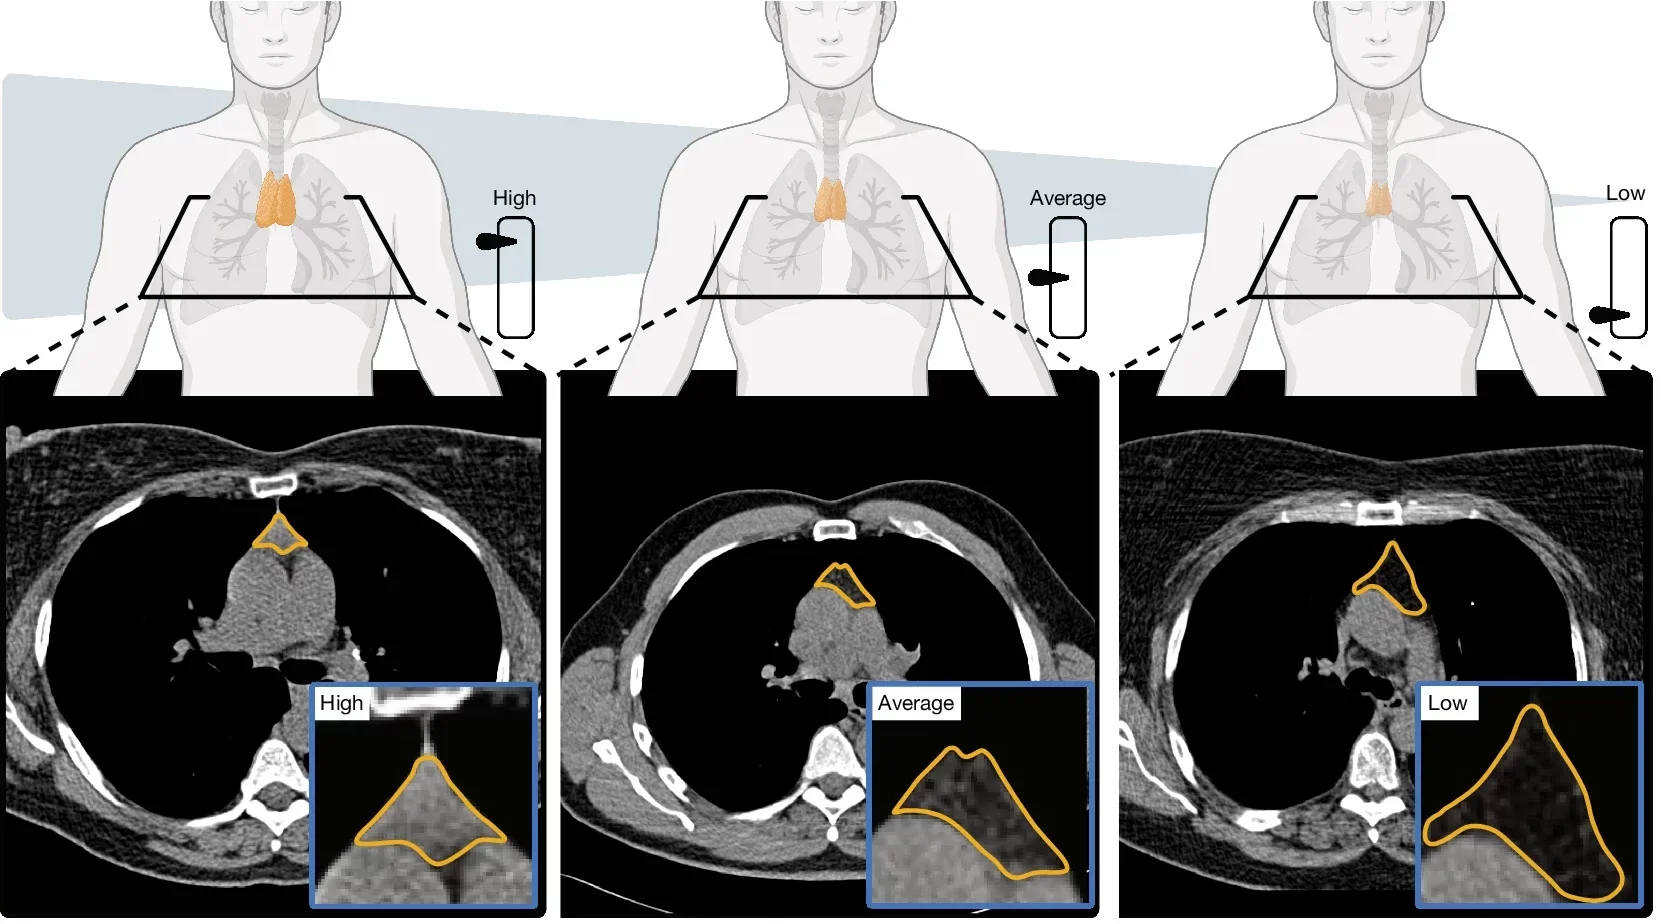

In the first study, the researchers analyzed CT scans from 27,612 adults drawn from two large groups: 25,031 people in the National Lung Screening Trial and 2,581 in the Framingham Heart Study. They used a deep learning system, developed on a separate dataset of 5,674 scans, to estimate “thymic health” based on the organ’s radiographic appearance.

That score was then sorted into three broad groups: low, average, and high.